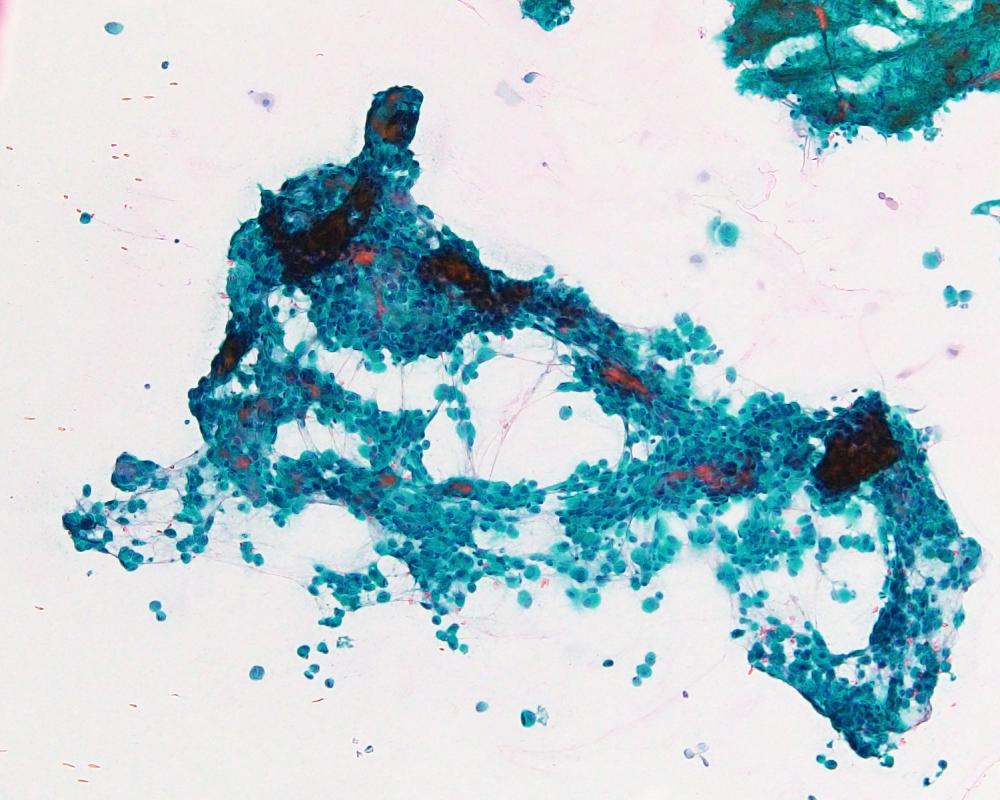

第40回日本臨床細胞学会九州連合会学会(大分)スライドカンファレンス症例2

種別:呼吸器

出題:今村 彰吾 独立行政法人国立病院機構九州がんセンター

| 年齢 | 50歳代 | 性別 | 女性 |

| 採取部位 | 気管支 | 採取方法 | 気管支鏡下生検捺印 |

既往歴 右頬粘膜癌(7年前)および肺転移(8年前)、歯肉癌(2か月前)

現病歴 右頬粘膜癌に対してニボルマブ投与中、PET-CTにて左気管支内に異常集積を指摘され、精査目的で当科紹介受診となった。

| 正解 | 5.間葉系腫瘍 |

▼選択肢及び投票結果

| 1.扁平上皮化生細胞 | 4件 | (3.8%) | |

| 2.扁平上皮癌 | 6件 | (5.7%) | |

| 4.非小細胞癌(肉腫様癌) | 35件 | (33.3%) | |

| 5.間葉系腫瘍 | 60件 | (57.1%) | |

| 投票総数 | 105件 | (100%) |